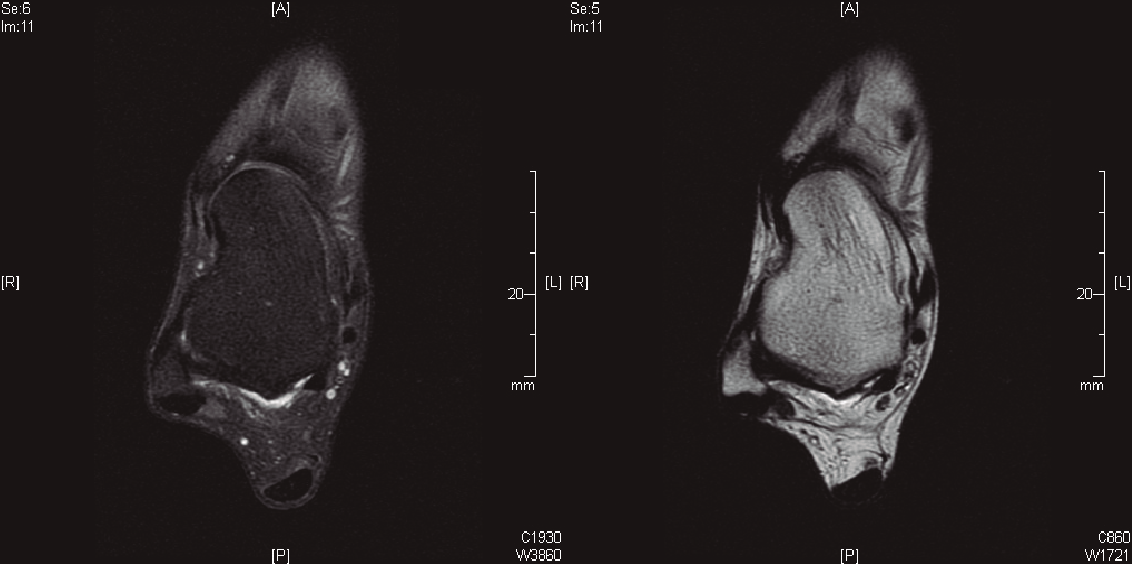

Respecto a los estudios radiológicos solicitados, las radiografías en carga en proyecciones dorsoplantar y lateral de ambos pies y tobillos no demostraron hallazgos de interés. No se solicitaron radiografías en estrés en varo-valgo, dado el poco valor diagnóstico que aportan. En la RMN no se observaba rotura del LPAA, pero sí anomalía en el mismo (Figura 1). No se encontraron lesiones asociadas. No se estimó necesaria la realización de una RMN con contraste.

Figura 1. Cortes axiales donde se observa integridad del ligamento peroneo astragalino anterior, aunque presenta una forma irregular.